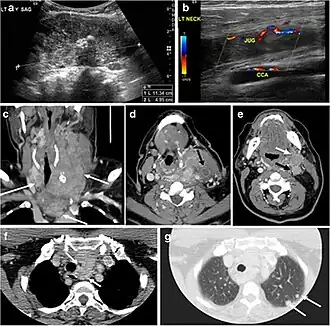

Fig. 6. A 61-year-old female patient with locally aggressive PTC. an Enhanced axial CT scan of the neck demonstrates a heterogeneous infiltrative thyroid mass. This mass diffusely involves the entire gland and circumferentially encases the trachea with involvement of bilateral tracheoesophageal grooves (white arrows). b, c Additional axial cranial images show right cricoid cartilage destruction (black arrows in b), right thyroid cartilage destruction (black arrow in c), right vocal cord paralysis (white arrows in b), and bilateral cervical lymphadenopathy (arrowheads).[1]

Fig. 13. A 27-year-old female patient known to have goiter. a, b Axial and sagittal enhanced CT scan images of the neck demonstrate a heterogeneously enhancing, enlarged thyroid gland with scattered calcifications (white arrow), cystic changes, and substantial retro-sternal extension (black asterisks). No lymphadenopathy or substantial airway narrowing.[1] -

Fig. 14. A 19-year-old male patient known to have multi-nodular goiter and FNA, showing underlying Hashimoto's thyroiditis. a, b Sagittal and transverse greyscale and colour Doppler ultrasound of the neck demonstrate a hypoechoic enlarged right thyroid lobe with small hyperechoic regenerative nodules and marked hypervascularity (white arrows). c, d Enhanced axial CT scan images of the neck demonstrate a heterogeneously enhancing and enlarged thyroid gland, left more than right lobe, and the trachea is markedly narrowed.[1] -

Fig. 15. A 33-year-old female patient who presented with neck swelling and pain and was later diagnosed with Hashimoto's thyroiditis. an Axial enhanced CT scan of the neck demonstrates minimal diffuse enlargement of the thyroid gland, especially the isthmus (white arrow). b Transverse greyscale ultrasound of the neck demonstrates heterogeneously enlarged thyroid and thickened isthmus, measuring 8.6 mm.[1]

Malignancy can coexist within the goiter and a CT scan may give a clue if there are abnormal cervical lymph nodes and/or signs of invasion. Retrosternal extension (Fig. 15) could affect the surgical approach, as a lower extent may require a partial or total sternotomy to facilitate complete resection. Therefore, the distance of the retrosternal extent from the sternal notch should be measured on a sagittal image.[1]

The interpreting radiologist should describe the mass effect, detailing its degree and direction of displacement of central structures, including the trachea, oesophagus, larynx, and pharynx. Attention should be directed to the upper extent of the goiter and structures immediately surrounding the thyroid gland, including the neuro-vascular structures, retropharyngeal space, and pre-vertebral space. The reporting radiologist should evaluate the vocal cords for symmetry and signs of vocal cord palsy.[1]